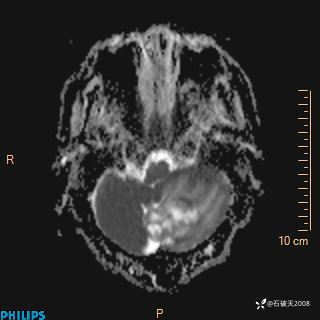

DWI